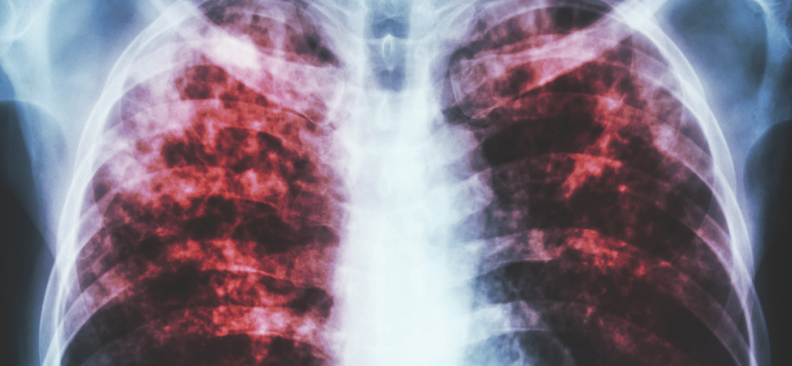

Pulmonary Fibrosis

04/22/2015

Jonathan S. Ilowite, MD, FCCP; Girish B. Nair, MD, FACP, FCCP

This article summarizes the clinical approach to diagnosis and treatment in a patient with IPF.